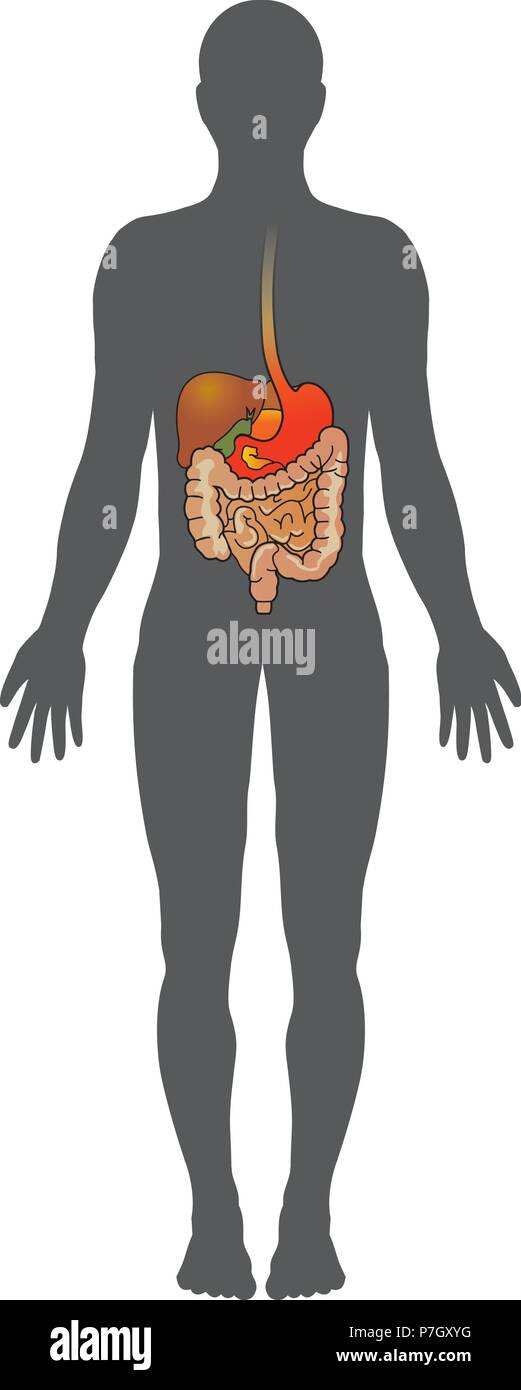

L'apparato digestivo umano è costituito dal tratto gastrointestinale plus l'accessorio organi della digestione. In questo sistema, il processo di digestione ha Illustrazione Vettorialehttps://www.alamy.it/image-license-details/?v=1https://www.alamy.it/l-apparato-digestivo-umano-e-costituito-dal-tratto-gastrointestinale-plus-l-accessorio-organi-della-digestione-in-questo-sistema-il-processo-di-digestione-ha-image211199396.html

L'apparato digestivo umano è costituito dal tratto gastrointestinale plus l'accessorio organi della digestione. In questo sistema, il processo di digestione ha Illustrazione Vettorialehttps://www.alamy.it/image-license-details/?v=1https://www.alamy.it/l-apparato-digestivo-umano-e-costituito-dal-tratto-gastrointestinale-plus-l-accessorio-organi-della-digestione-in-questo-sistema-il-processo-di-digestione-ha-image211199396.htmlRFP7GXYG–L'apparato digestivo umano è costituito dal tratto gastrointestinale plus l'accessorio organi della digestione. In questo sistema, il processo di digestione ha